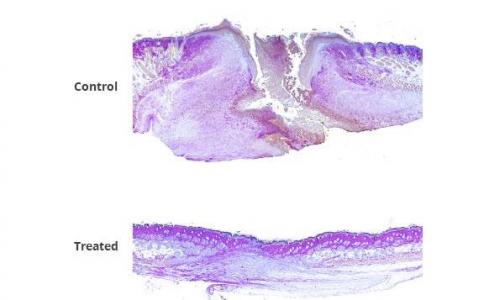

La preuve chez la souris : la combinaison FL2-siRNAs / PluroGel appliquée à des souris présentant des excisions cutanées ou des brûlures permet, à 4 jours post-traitement, de réduire la taille de la plaie d’excision de moitié. Plusieurs souris traitées par la thérapie combinée présentent également des follicules pileux sur l’ex site de la plaie, alors qu'aucun n’est observé chez les souris témoins. Et, chez les souris traitées pour brûlures, 14 jours après la lésion, les plaies des souris traitées sont réduites d’environ un tiers. En outre, les plaies de brûlure de toutes les souris traitées avec la combinaison FL2-siRNA / PluroGel sont totalement cicatrisées à 14 jours, vs seulement 25% à 30% chez les souris témoins.